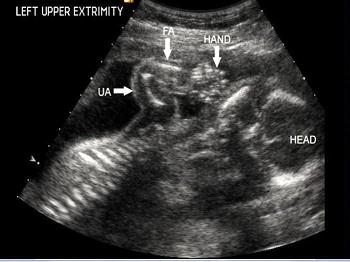

超声检查如图,最可能的诊断是?(?)A.致死性骨发育不全B.内翻足C.羊膜带综合征D.骨硬化症E.并指(趾)畸形

问题 超声检查如图,最可能的诊断是?(?)

选项 A.致死性骨发育不全 B.内翻足 C.羊膜带综合征 D.骨硬化症 E.并指(趾)畸形

答案 A